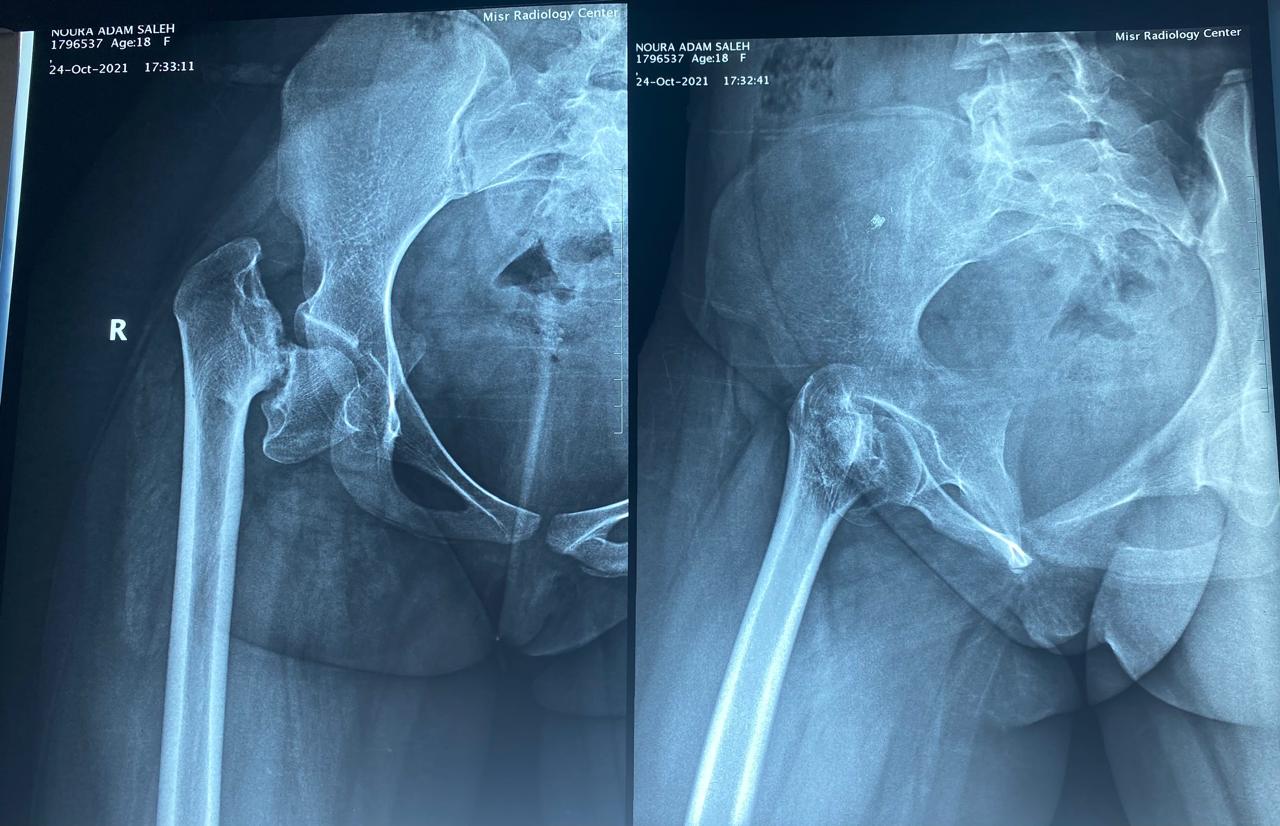

أشعة لمفصل الحوض تبين كسر قديم مهمل كما تبين وجود قصر شديد بالطرف السفلي.